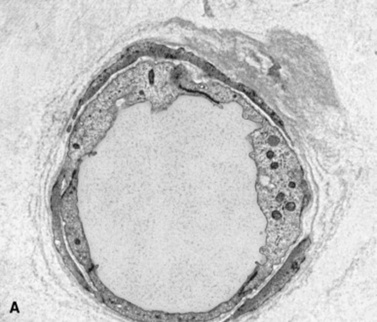

Ultrasound evaluation of horses with abdominal pain (colic) provides a rapid method to identify abnormalities within the gastrointestinal tract. Distention of the small intestine to a diameter greater than 5 cm has been strongly associated with strangulating or obstructing lesions19 (Fig. 32-11). In foals with intussusception, the small intestine appears enlarged and there is generally distended small intestine orad to the lesion; however, at the site of the intussusception there is a normal-appearing small intestinal wall (intussuscipiens) surrounded by a larger structure that appears to surround the inner small intestinal wall (called the intussusceptum)19 (Fig. 32-12). Large colon torsion occurs when the large colon rotates 360 degrees or more around the root of the mesentery to cause occlusion of venous drainage while maintaining arterial flow. This causes the wall to become thick and edematous. If ultrasound is performed in the cranioventral abdomen, just caudal to the xiphoid process, then a colon wall size greater than 9 mm is 100% specific for a large colon torsion21 (Fig. 32-13). A large colon displacement would have minimal to no vascular compromise, so it would be an ultrasound diagnosis based on exclusion. Chronic displacements did have a mild amount of edema in the colon wall, causing the size to be approximately 7 mm thick but never greater than 9 mm in the one study described.21 The colon and small intestinal wall will also become thick with inflammation. Small intestinal wall thickness greater than 4 mm is indicative of inflammation.19 The right dorsal colon can be imaged in the right tenth to twelfth intercostal space around the region of the costochondral junction, and a focal wall thickness of 9 to 12 mm has been identified with right dorsal colitis.23

Fig. 32-13 Transabdominal ultrasound images of the large colon. A, In colon torsion the large colon wall is severely thick (2 cm) secondary to edema. For comparison, a normal colon wall thickness (B) should be 0.2 to 0.4 cm in thickness.